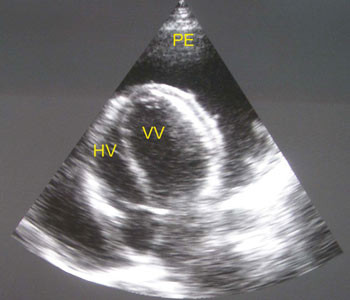

Pasienten ble overført til regionssykehus. Ekkokardiografi bekreftet en svær perikardeffusjon med fibrintråder typisk for tuberkuløs perikarditt (fig 2), og tegn på hjertetamponade. Det ble gjort perikardiocentese og tappet 750 ml blodig perikardvæske. Tilstanden bedret seg umiddelbart, og pasienten ble på empirisk grunnlag gitt antituberkuløs behandling og prednisolon.

Denne sykehistorien er vanlig i land der hiv og tuberkulose er svært utbredt. Den viser at differensialdiagnostikken ved kardiomegali kan være vanskelig, og at ekkokardiografi, når undersøkelsen er tilgjengelig, ofte er avgjørende for diagnose og behandlingsvalg. Dessverre er tilgangen på kardiologisk ekspertise og ekkokardiografi dårlig eller ikke-eksisterende for store deler av befolkningen i Afrika.

Røntgen thorax viser kardiomegali hos 90 %, og rundt 30 % har samtidig tegn på pulmonal tuberkulose. EKG kan gi viktig tilleggsinformasjon med low voltage, STT-forandringer eller elektrisk alternans (21, 23). Ekkokardiografi gir en sikker diagnose ved perikardeffusjon. Tilstanden utvikler seg over tid og perikard tøyes. Derfor kan man se svære effusjoner med flere liter perikardvæske uten at det foreligger hjertetamponade.